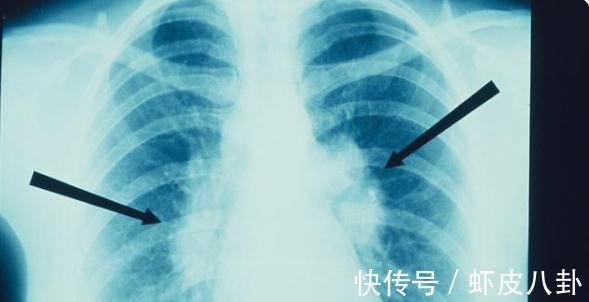

通常当肺结节≤4mm时,一年复查;肺结节4-6mm时,半年复查;肺结节6-8mm时3个月复查,对于大于8mm的肺结节如果影像学提示恶性可能性较大时可以手术切除。